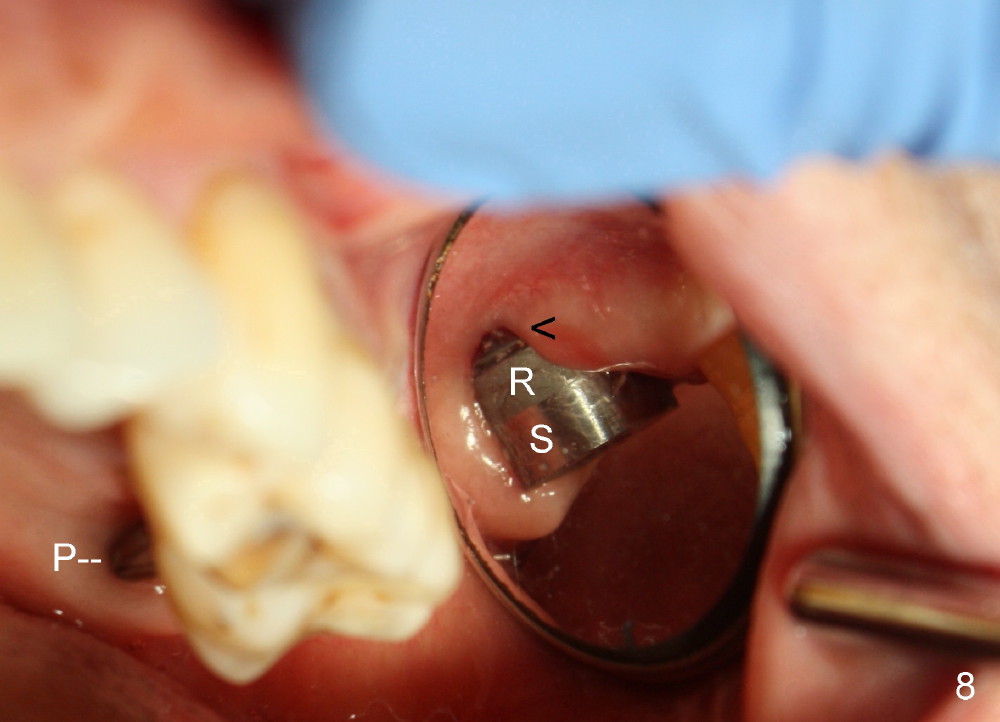

Next time she returns 4.5 months postop, bone looks normal around the implant (Fig.7), whereas the buccal gingival recession appears to get worse with 1-2 implant thread exposure (Fig.8 >). To avoid this complication, the initial osteotomy should be placed as palatal as possible; when the implant is placed with gingival recession (Fig.5), soft tissue graft should be performed. The implant should be smaller.